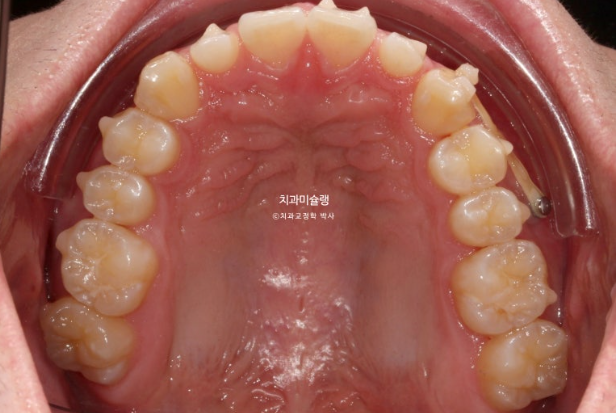

파란 화살표가 가위교합이고 위 큰어금니는 바깥으로 나가있고 대합치는 안쪽으로 쓰러지며 가위처럼 서로 엇갈려 교합되는 상태를 말합니다.

파란 화살표 치아가 바깥으로 뻗치면서 가위교합의 원인이 됩니다.

치료 목표는 치아 중심선을 얼굴중심으로 끌어오기 위해 편측 사랑니 공간을 이용한 후방이동, 이때 교정용 나사인 미니스크류가 필요하겠죠.

그리고 교정 후 왜소치 무삭제라미네이트 젤라미 수복입니다.

사랑니를 모두 발치하고 인비절라인으로 치료를 시작했습니다.

가위교합은 해결이 되었지만 아직 어금니 교합이 긴밀하지 않습니다.

배열은 완벽합니다.

중심선 등을 좀 더 바로잡고자 재제작에 들어갑니다.